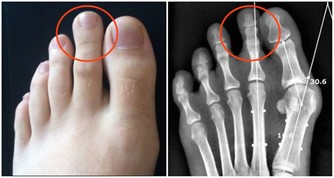

如果雙手是能一窺健康的門戶,那位於手足之端、也就是經脈終始點的井穴,就是身體與外界溝通的窗口。《黃帝內經。靈樞》將井穴喻為水之源頭,是精氣所出的部位,對於調節臟腑、氣血、經脈之氣有相當重要的作用。裡頭也提到,「病在臟者取之井」。顯見,透過井穴,可以治療相應臟腑的疾病。

循著連接手指的六條經絡及其相應經氣,大拇指的少商穴對應肺、脾食指的商陽穴對應大腸、胃中指的中沖穴對應心包、肝無名指的關沖穴對應三焦、膽小指的少澤穴對應心、腎少沖穴對應小腸、膀胱。

井穴有清熱、醒腦、安神的作用,平時醫師會藉由放血、針灸達到治療效果,中醫則建議,一般民眾平時可以透過井穴按摩來保養身體,精神不濟時,開過十指井穴也能活絡臟腑、重拾元氣。

開井穴依序是,按壓手指第一個指節以上的指甲兩側,然後再捏緊指甲上下方的指頭,一指大概20秒,十指開過只需要三分多鐘,就能有效刺激。